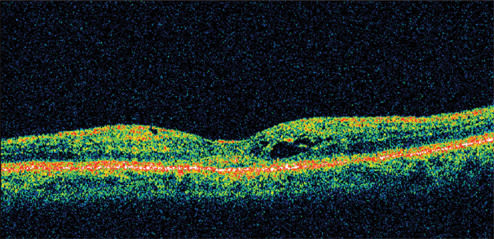

A 71-year-old man who had cataract surgery 3 months earlier was a known steroid responder with elevated IOP following surgery. At presentation, his visual acuity was 20/63. He had a fine epiretinal membrane and CME OD. Retinal thickness was 501 μm on OCT (Figure 4).

Figure 4. A 71-year-old man, who had cataract surgery 3 months earlier, presented with visual acuity of 20/63. He had a fine epiretinal membrane and CME OD. Retinal thickness was 501 μm on OCT.

He was treated with nepafenac qid for 6 weeks and tapered over the ensuing 6 weeks. His vision improved to 20/32 by 1 month, with a marked reduction in retinal thickness. By 12 weeks, his visual acuity was still 20/32 with retinal thickness of 261 μm and an improvement in the appearance of the fovea (Figure 5).